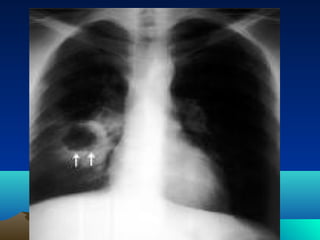

role

Only in life threatening

condition

(mass effect)